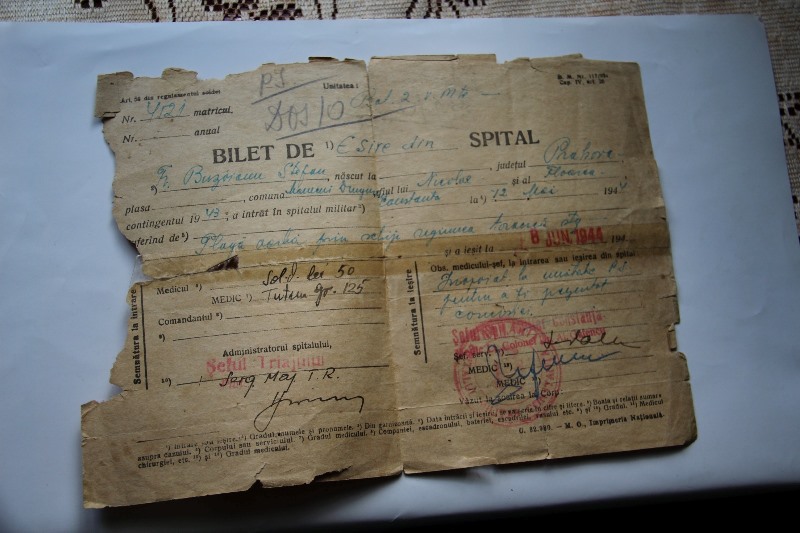

Ori de câte ori este întrebat de momentele trăite la ruși, nu omite episodul în care a fost „vizitat“ de moarte și în care s-a trezit cu un glonț în spinare. Un glonț care i-a perforat plămânul și i-a ajuns lângă inimă. A fost scos din tabăra de luptă și târât de ceilalți soldați pe o poiană de unde a fost preluat de sanitari.

„Rana a simțit-o ca pe o arsură, o căldură, după cum ne-a povestit. A zăcut într-un șanț, în stare de semi conștiență, recuperat de sanitarii din spatele liniei de front. A avut noroc că în retragere a trecut un camion unde a fost înghesuit cu alți răniți. A ajuns pe o plajă unde așteptau îmbarcarea și unde a stat o noapte. Când au sosit vapoarele a fost consultat de un medic german, care l-a curățat și pansat în condițiile de atunci. Era rănit în zona plămânului și respira foarte greu. Apoi, a fost improvizat un fel de ponton și, când i-a venit rândul să plece, aviația rusă a început bombardarea vaselor", ne-a povestit Dragoș Buzoianu, nepotul veteranului.

„A fost balamuc mare. Spitalul de campanie era format din niște barăci, eram ținuți pe paie, a fost vai de noi. Eu respiram întrerupt, dar am avut zile. Am stat peste o lună în spital, iar, ulterior, comisia de evaluare a decis să revin pe front“, ne-a mai spus nea Ștefan. A rămas pe linia Dunării, iar de aici încep alte povești despre pândă, despre contrabadiști ai acelor vremuri pe care i-a depistat.